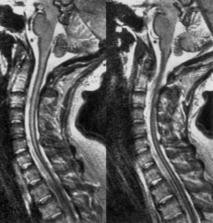

Um die Diagnose zu bestätigen, kann der Arzt verschiedene bildgebende Verfahren anwenden. Eine der häufigsten Methoden ist die Röntgenaufnahme der Lunge. Diese kann helfen, Anzeichen von Eisenansammlungen in der Lunge zu erkennen. In einigen Fällen kann auch eine Computertomographie (CT) oder Magnetresonanztomographie (MRT) erforderlich sein, um detailliertere Bilder der Lunge und anderer betroffener Organe zu erhalten.